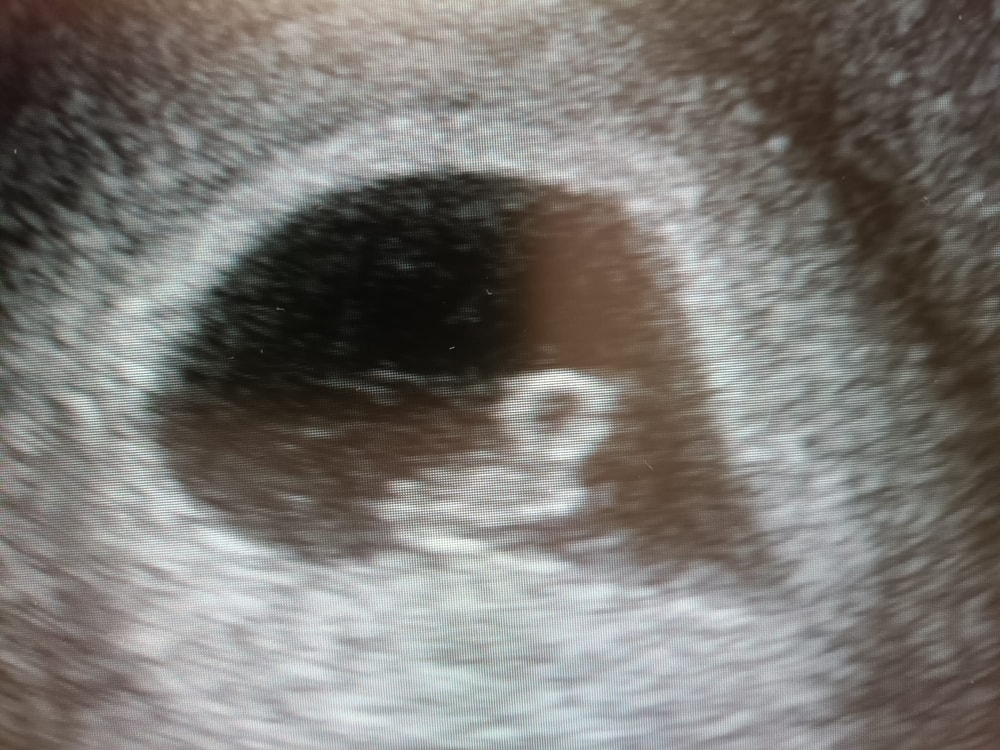

Вот уже и 8 недель, время очень странно идёт , вроде медленно, а вроде , как уже месяц прошел?? ☺️